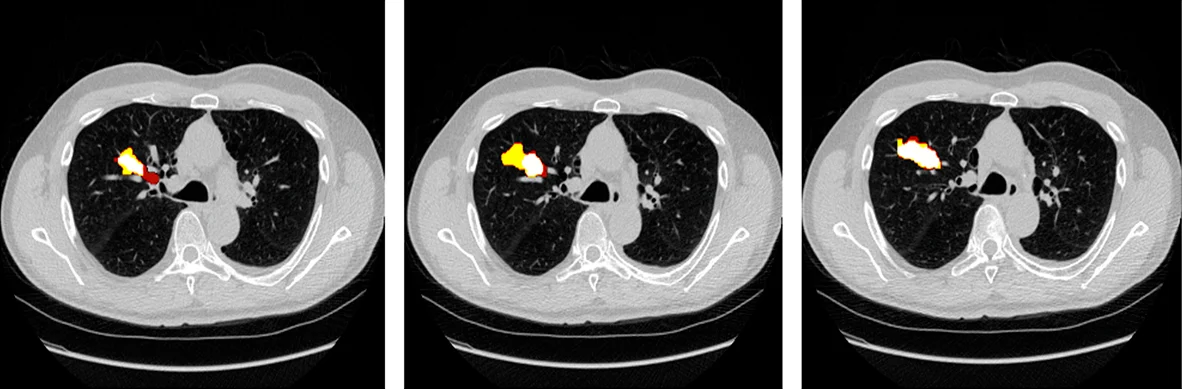

Medical imaging is one of the most data-intensive areas in oncology AI.

To enable AI models to interpret these images accurately, they must be annotated with extreme precision.

This is where medical image annotation for AI becomes essential.

High-quality medical image annotation ensures AI systems learn clinically relevant features rather than noise.

Through detailed and structured annotation processes, Pareidolia empowers AI models in:

High-quality annotation also helps AI development teams better interpret model outputs, enabling clearer visualization of detected regions and improving collaboration between data scientists and clinical experts.